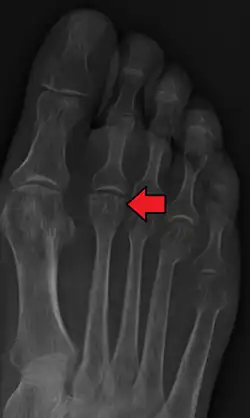

- Radiography: X-rays may reveal flattening, sclerosis, or fragmentation of the metatarsal head.

- Magnetic Resonance Imaging (MRI): Provides detailed images of soft tissue and bone changes, particularly useful in early stages of the disease.